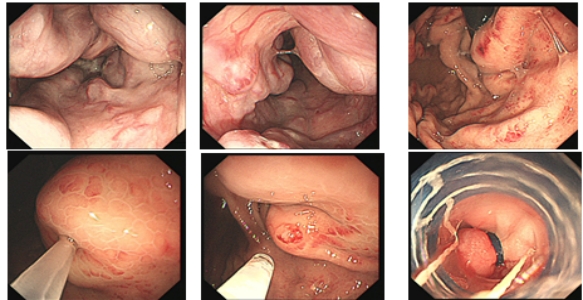

早期胃癌及内镜手术

早期食管癌及内镜手术

结肠息肉及内镜手术

胃、食管、肠粘膜下肿瘤切除术(ESE、EFTR、STER)

消化道早癌的病例展示(经内镜手术或活检证实):

胃角的腺癌

胃窦的微小腺癌

胃窦印戒细胞癌

十二指肠降段早癌

胃窦的腺癌 行ESD治疗

术中见较粗穿支血管,裸化后凝除,最终高效、安全的切除病灶。

结肠腺瘤的ESD手术

十二指肠溃疡降段早癌的内镜粘膜剥离手术治疗(ESD)

直肠巨大侧向发育型肿瘤,内镜下完整切除(ESD),术后病理证实粘膜内癌,不需追加治疗,达到治愈目的,保留正常器官,避免外科手术。

胃内4x4cm粘膜下隆起,胃镜下完整切除(ESE),术后病理证实平滑肌瘤,保留胃正常组织结构。